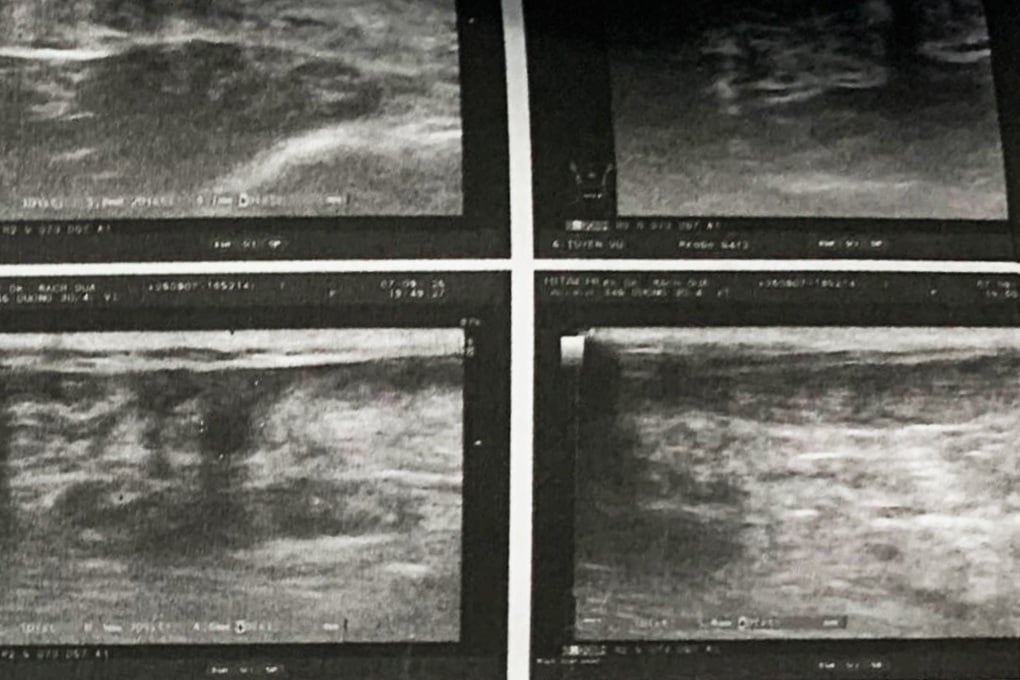

លទ្ធផលនៃការថតរូបបានបង្ហាញថា អ្នកជំងឺមានសរសៃពួរ Achilles រហែកទាំងស្រុង ហើយត្រូវការការវះកាត់សរសៃពួរ។

រូបភាពកាំរស្មីអ៊ិចបង្ហាញថាអ្នកជំងឺមានសរសៃពួរ Achilles រហែកទាំងស្រុង (រូបថត៖ វេជ្ជបណ្ឌិត) ។